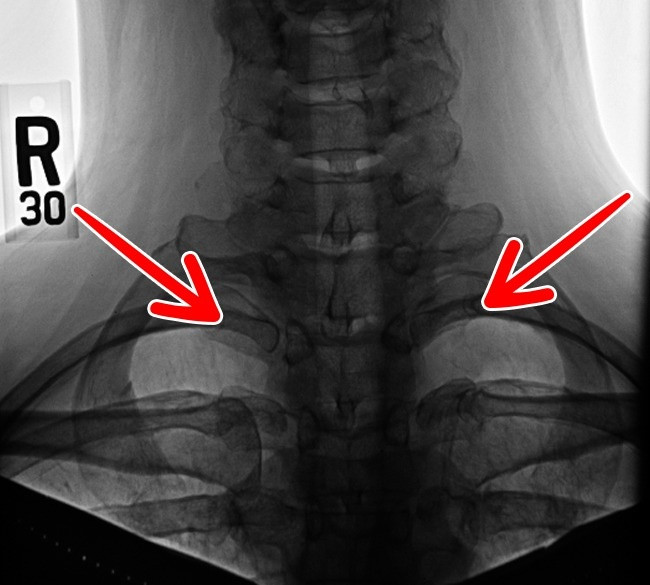

5.  Xương sống cổ

15 bộ phận trên cơ thể con người sẽ biến mất trong tương lai ảnh 5

Xương sống cổ - một bộ phận sót lại từ thời bò sát chỉ còn trong 1% dân số. Một số người có nó ở bên trái hoặc bên phải. Một số người khác có cả ở hai bên. Nó thường gây ra các vấn đề về thần kinh và động mạch.